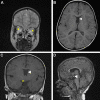

Nailing septo-optic dysplasia